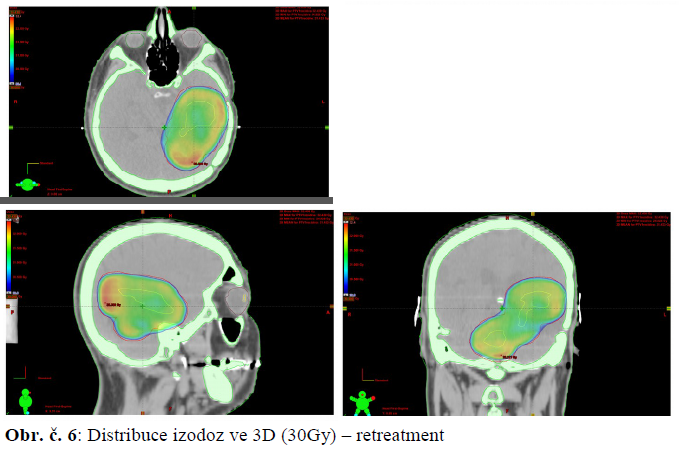

12.6.-1.7.2014: konkomitantní chemoradioterapie:

- a) Temodal 140mg denně v průběhu RT

- b) X záření 6 MV tech. IMRT na oblast recidivy, d. l. d. 2Gy do celk. d. 30Gy

5.6.2014 mailová konzultace s doc. RNDr. P. Matulou s kontrolním výpočtem BioGray:

…. Pri reožarovaní môžete dodať až 140 % pôvodnej dávky, tzn. pri 60 Gy po 2 rokoch až 20F/2 Gy = 40 Gy.

Výstupy toto tvrdenie z literatúry potvrdujú.

Reporty su vztiahnuté na pauzy 427 dní , kedy regenerácia nie je ešte saturovaná a 593 dní, kde sa dosiahla regenerácia na úroveň 140 %